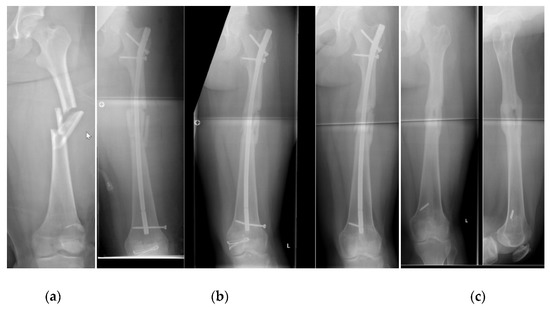

4.2. Demographics, Radiographic Analysis and Complications

| ALFN as the primary treatment or as a revision | |||||||||||||||||||

| ALFN used for revision of otherwise failed fixation | 1 | 11% | 1 | 17% | 2 | 13% | |||||||||||||

| ALFN used as primary fixation | 8 | 89% | 5 | 83% | 13 | 87% | |||||||||||||